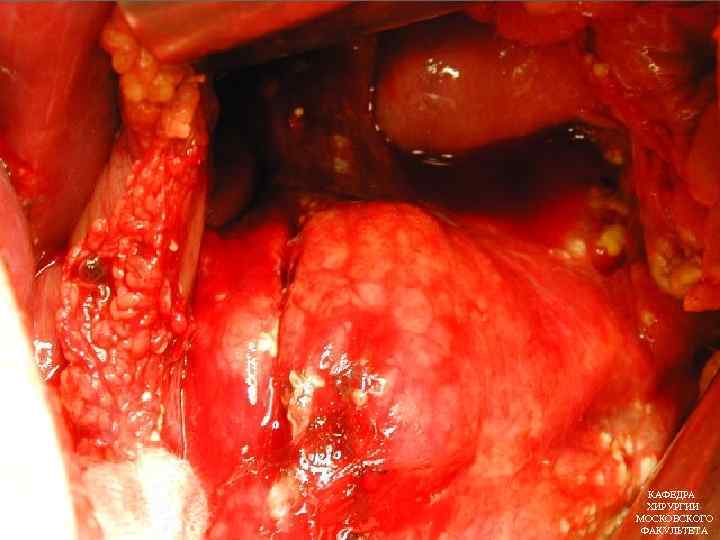

ПОКАЗАНИЯ К ХИРУРГИЧЕСКОМУ ЛЕЧЕНИЮ ПАНКРЕОНЕКРОЗА Инфицированный панкреонекроз Прогрессирующая полиорганная недостаточность Наличие деструктивного холецистита Ферментативный перитонит КАФЕДРА ХИРУРГИИ МОСКОВСКОГО ФАКУЛЬТЕТА

ПОКАЗАНИЯ К ХИРУРГИЧЕСКОМУ ЛЕЧЕНИЮ ПАНКРЕОНЕКРОЗА Инфицированный панкреонекроз Прогрессирующая полиорганная недостаточность Наличие деструктивного холецистита Ферментативный перитонит КАФЕДРА ХИРУРГИИ МОСКОВСКОГО ФАКУЛЬТЕТА

ВИДЫ ОПЕРАТИВНЫХ ВМЕШАТЕЛЬСТВ ПРИ ПАНКРЕОНЕКРОЗЕ ОРГАНОСОХРАНЯЮЩИЕ капсулотомия РЕЗЕКЦИОННЫЕ марсупиализация некрэктомия оментопанкреатопексия секвестрэктомия абдоминизация железы резекция поджелудочной дренирование сальниковой железы сумки панкреатэктомия дренирование кист панкреатодуоденальная люмботомия резекция КАФЕДРА ХИРУРГИИ МОСКОВСКОГО ФАКУЛЬТЕТА

ВИДЫ ОПЕРАТИВНЫХ ВМЕШАТЕЛЬСТВ ПРИ ПАНКРЕОНЕКРОЗЕ ОРГАНОСОХРАНЯЮЩИЕ капсулотомия РЕЗЕКЦИОННЫЕ марсупиализация некрэктомия оментопанкреатопексия секвестрэктомия абдоминизация железы резекция поджелудочной дренирование сальниковой железы сумки панкреатэктомия дренирование кист панкреатодуоденальная люмботомия резекция КАФЕДРА ХИРУРГИИ МОСКОВСКОГО ФАКУЛЬТЕТА